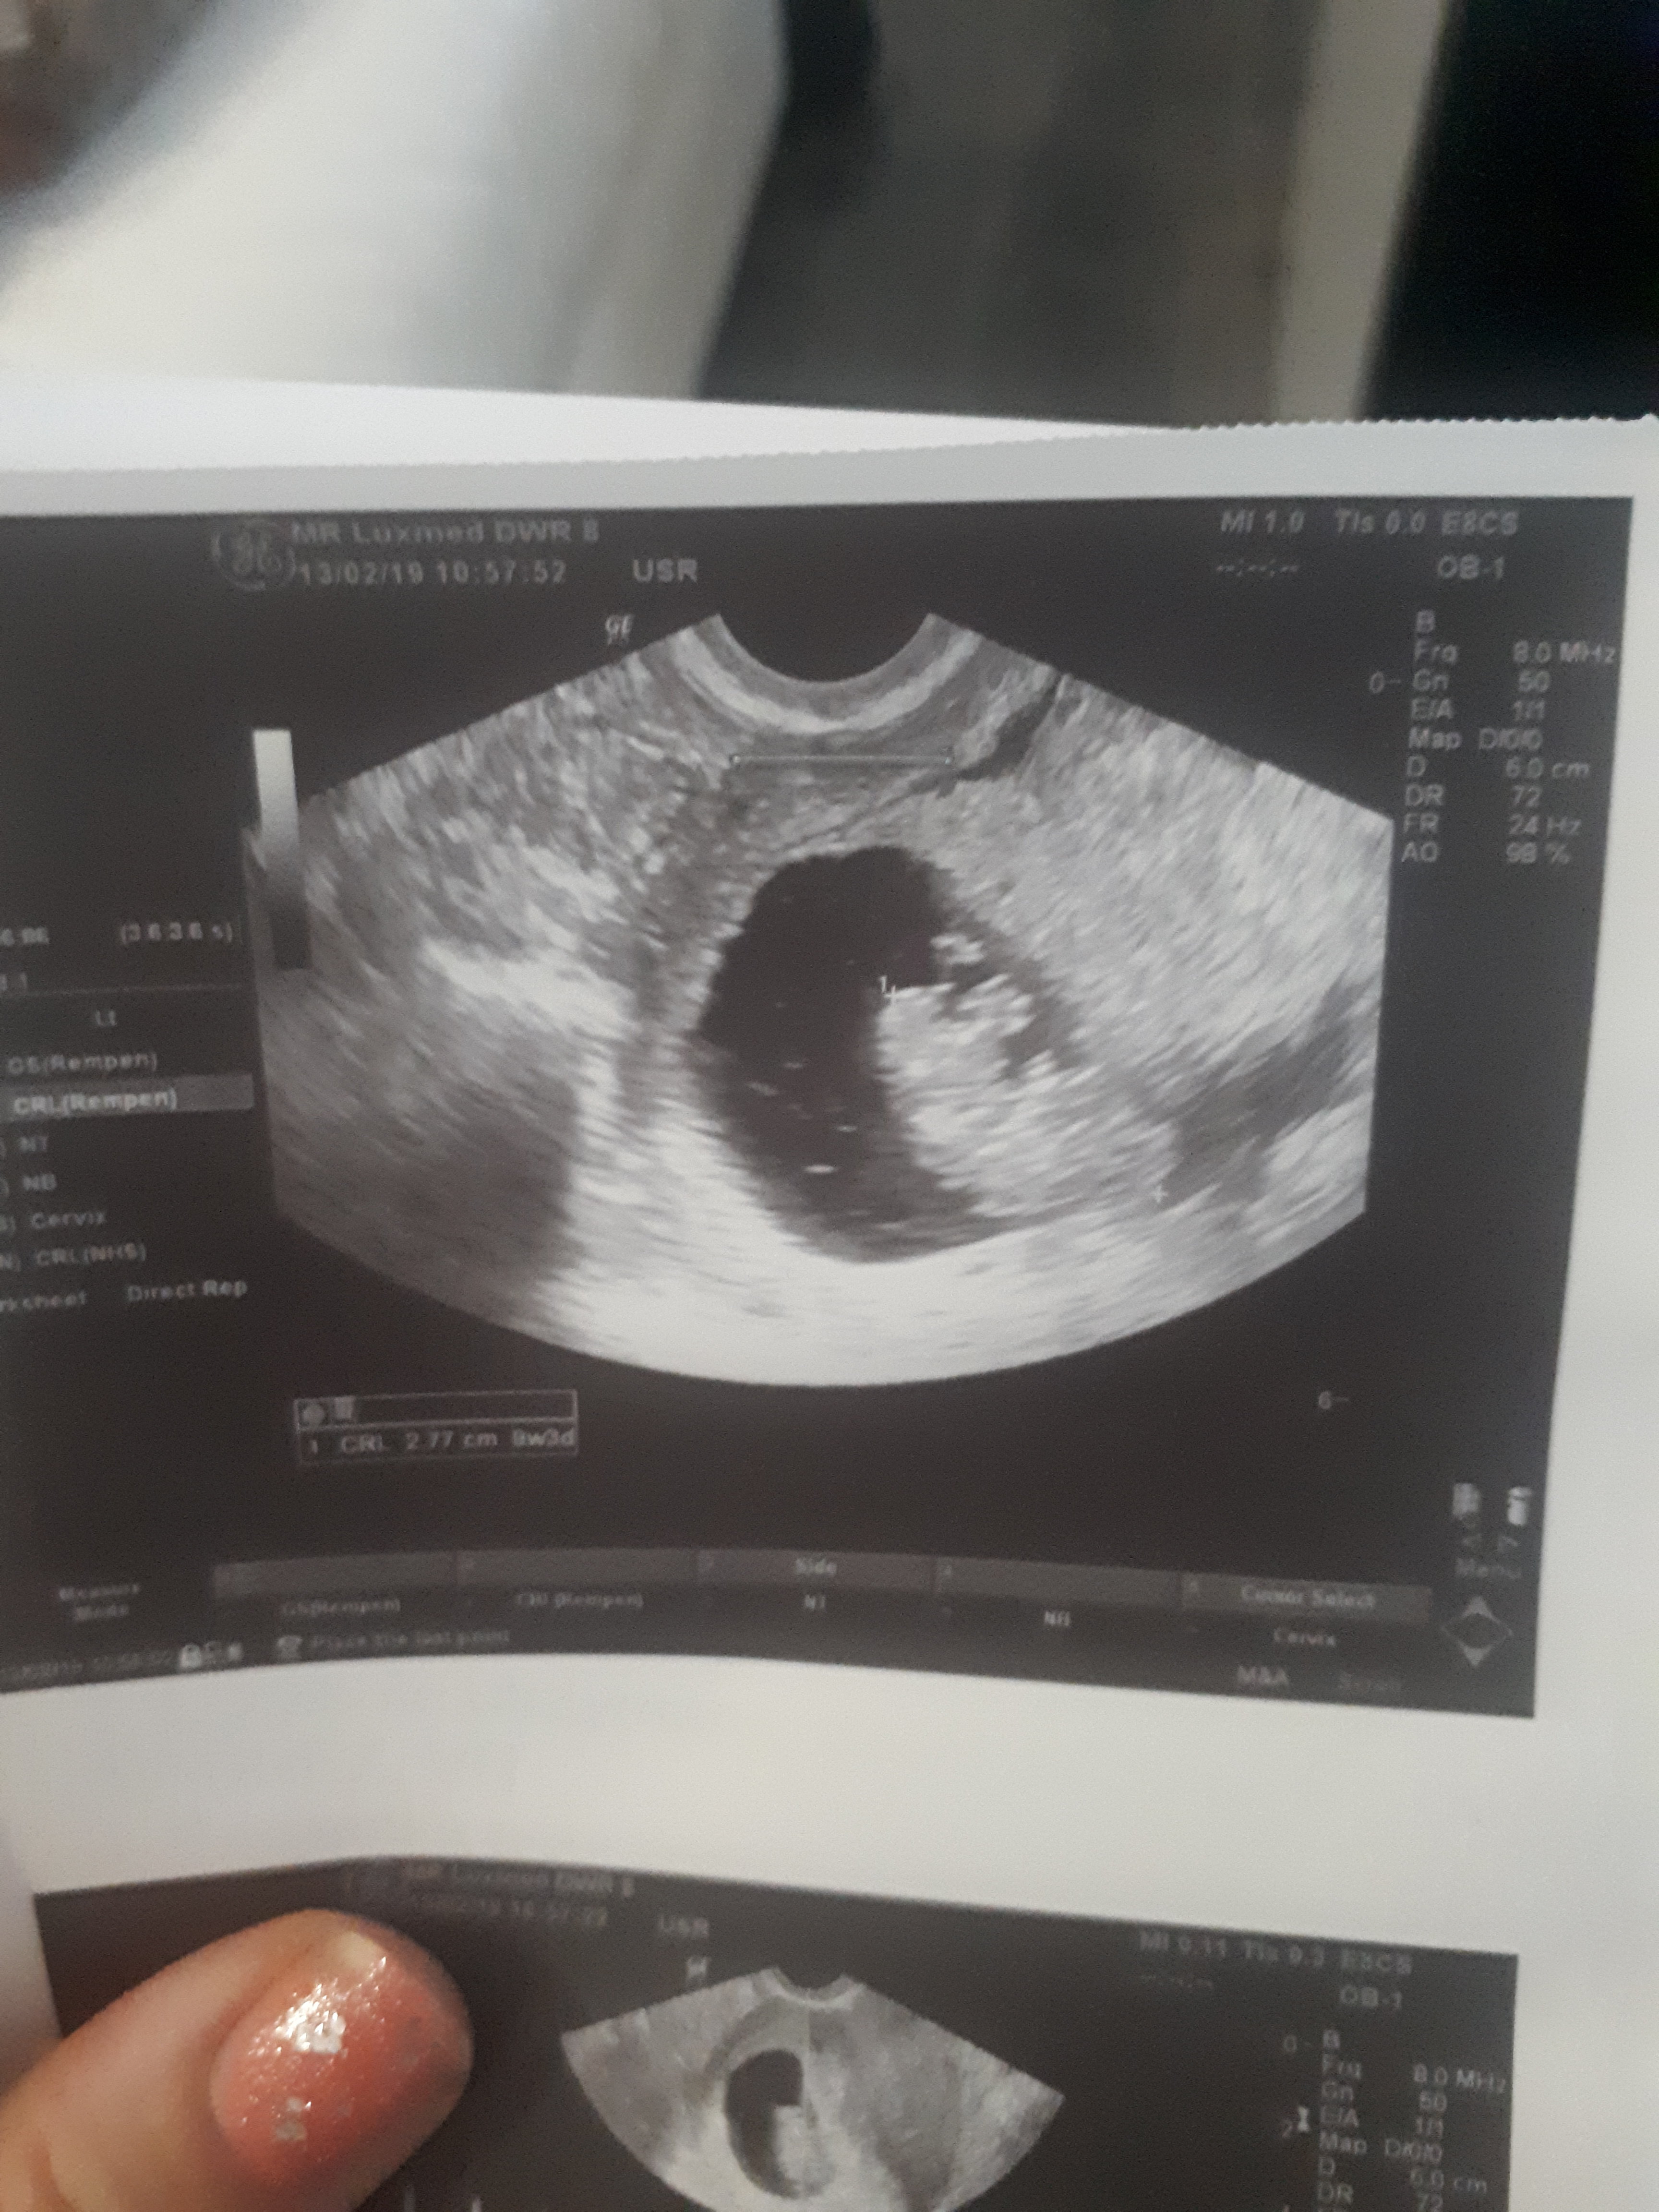

Ja już po badaniu[emoji16] ryzyko chorób genetycznych małe, serduszko bije 166 uderzeń, nt 1,09

Nic więcej nie wiem[emoji16]wizyta może z 5 min trwała, pomierzył popisał i kolejna ehh..polski NFZ...